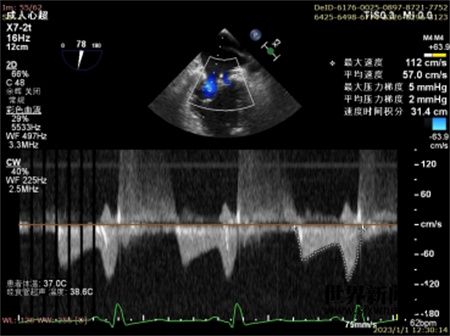

术前结合病变解剖特点,详细制定手术方案,拟用1枚XTR处理2区偏1区的返流,改善瓣叶对合情况。在经食道指导下穿刺房间隔(房间隔穿刺点距二尖瓣环4cm-5cm),(图4)通过超硬导丝置入24F可操控导引导管至左心房后,送入二尖瓣夹输送系统,在超声引导下调节二尖瓣夹输送系统指向二尖瓣口反流最明显处并能垂直活动,打开二尖瓣夹的双臂至120°,在经食道超声(左室流出道和心尖两腔心切面)指导下调整二尖瓣夹使之位于二尖瓣前后瓣叶的中间,实时3维超声外科视野切面下进一步调整二尖瓣夹至二尖瓣瓣环中间,并调整使两臂位于6点半和12点半;于心脏舒张期送入心室腔,缓慢回撤二尖瓣夹,并使2个瓣叶均落在二尖瓣夹的两个臂上,操作二尖瓣夹使之夹住2个瓣尖(图5),经食道超声反复确认二尖瓣反流明显减轻降至1+(图6),二尖瓣平均跨瓣压差仅2mmHg(图7)且组织桥稳定(图8),最终释放二尖瓣夹,退出二尖瓣夹输送系统和24F可操控导引导管,8字缝合股静脉。